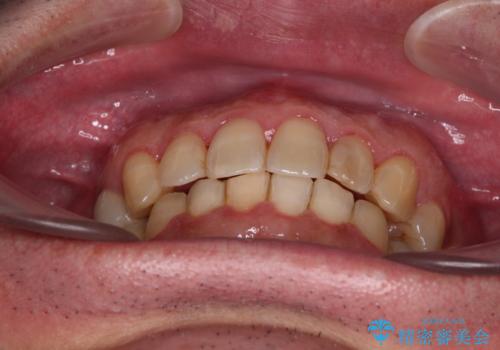

治療途中で1年半以上通院されない時期があったため、後戻りが生じたことで治療期間が長くなってしまいました。

親知らずを抜去したことで、下顎のデコボコがきれいに解消されました。